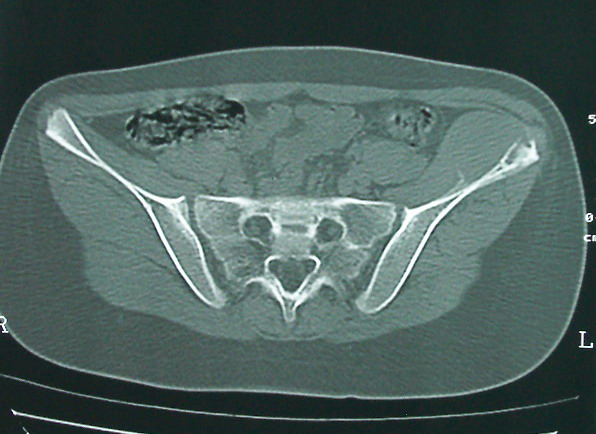

女 13岁 4月前有臀部肌肉注射史 3月前发热 最高体温38.5 2月前出现左髂骨疼痛 不剧烈能忍受 发热时高时低 按感冒治疗无好转 近日左髂骨疼痛加重 一星期前wbc 12.2 今日wbc9.5

左侧髂骨溶骨性骨质破坏,骨皮质侵蚀,灶周可见软组织肿块,支持考虑骨肉瘤可能性大。

髓腔起源,弥漫性溶骨性骨质破坏并软组织肿块,膨胀不明显,无显著钙化及瘤骨,有骨膜反应,结合年龄考虑恶性,尤文氏肉瘤可能性大。

鉴别:尤文氏肉瘤>毛细血管扩张型骨肉瘤>骨原发淋巴瘤>朗格罕氏细胞增生症>软黏纤>慢性骨髓炎>tb。

左侧髂骨溶骨性骨质破坏,骨皮质侵蚀,灶周可见软组织肿块

支持髂骨低毒性骨髓炎或骨结核:骨质破坏,髂腰肌明显肿胀,非长管状骨部位。

左侧髂骨溶骨性骨质破坏,骨皮质侵蚀,灶周可见骨膜反应及软组织肿块,支持考虑骨肉瘤可能性大。